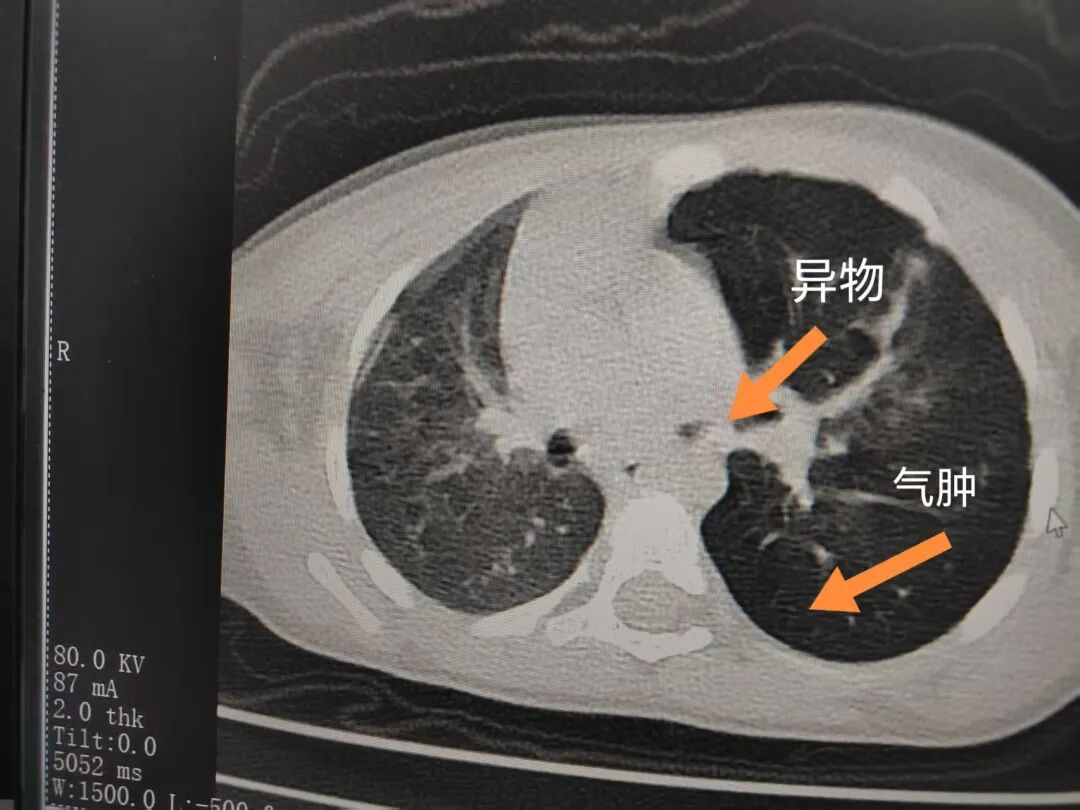

三天后(11月13日),趙寶出現(xiàn)高熱、咳喘加重,家長(zhǎng)著急了,再次帶他來(lái)到醫(yī)院。CT檢查顯示左肺過(guò)度充氣,左肺上下葉支氣管主干見(jiàn)不規(guī)則高密度影,左肺上葉可見(jiàn)大片狀密度增高影,縱隔窗實(shí)變,提示為“左側(cè)支氣管內(nèi)異物并繼發(fā)性改變,左肺上葉舌段肺膨脹不全”。